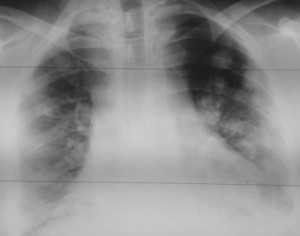

Как выглядят метастазы в легких на рентгене? Слева — узловые образования у пациента с раком яичка. Справа - метастазы рака яичников гематогенного характера с выраженным опухолевым лимфангиитом (обратите внимание на деформированный сетчатый, линейный характер легочного рисунка).

Обратите внимание на увеличение и нарушение структуры корня правого легкого. Это центральный рак. Кроме того, выявлены очаговые тени в обоих легочных полях (гематогенное распространение), а также «лучи», идущие радиально от опухоли корня (лимфогенное распространение).